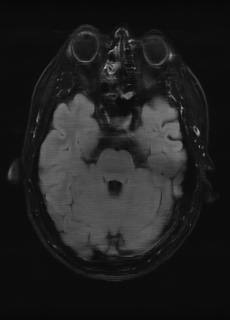

As we observe from the right image in Fig. 2, our BRM, both from MIMO and SISO settings, predicts the performance of dedicated models with a high correlation. We further choose the best three , and perform the last stage of fine-tuning accordingly to (6). A visual evaluation on real data is shown in Fig. 3. For simulated data, please refer to the Supplemental Material section.

Base on the best performing , we perceive that among , , and FLAIR, the results are best when is sampled the most. We suggest that this makes intuitive sense as images provide the best contrast out of the three sequences, which can compensate for the details lost in other images. The same observation can be made on the simulated data, where both and FLAIR show good contrast. When the time setting is changed to non-uniformity, we can see that our search for the best sampling strategy reflects the change. is sampled more as a result of faster acquisition time, while is still sufficiently sampled.

(a) 34.38/0.9371

(a) 34.38/0.9371

|

(b) 42.42/0.9883

(b) 42.42/0.9883

|

(c) 44.60/0.9920

(c) 44.60/0.9920

|

(d) 45.50/0.9940

(d) 45.50/0.9940

|

(e) PSNR/SSIM

(e) PSNR/SSIM

|

|

(f) 29.74/0.8903

(f) 29.74/0.8903

|

(g) 36.25/0.9734

(g) 36.25/0.9734

|

(h) 36.42/0.9752

(h) 36.42/0.9752

|

(i) 37.70/0.9832

(i) 37.70/0.9832

|

(j) PSNR/SSIM

(j) PSNR/SSIM

|

|

(k) 39.89/0.9311

(k) 39.89/0.9311

|

(l) 43.94/0.9864

(l) 43.94/0.9864

|

(m) 44.74/0.9883

(m) 44.74/0.9883

|

(n) 45.49/0.9894

(n) 45.49/0.9894

|

(o) PSNR/SSIM

(o) PSNR/SSIM

|